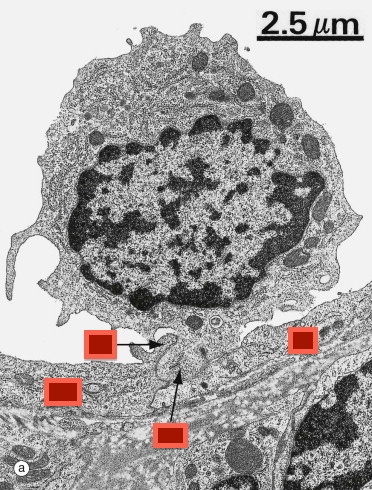

What is this cell?

Lymphocyte and endothelium